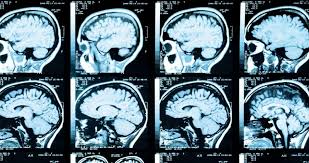

모야모야병은 증상과 병력을 바탕으로 의심되며, 다음의 영상 검사를 통해 진단이 확정됩니다.

① MRI 및 MRA(자기공명혈관조영술)

- 뇌혈관의 좁아진 부위 및 대체 혈관망(모야모야 혈관)을 시각화함

- 뇌조직의 손상, 허혈 또는 출혈 여부도 동시에 확인 가능